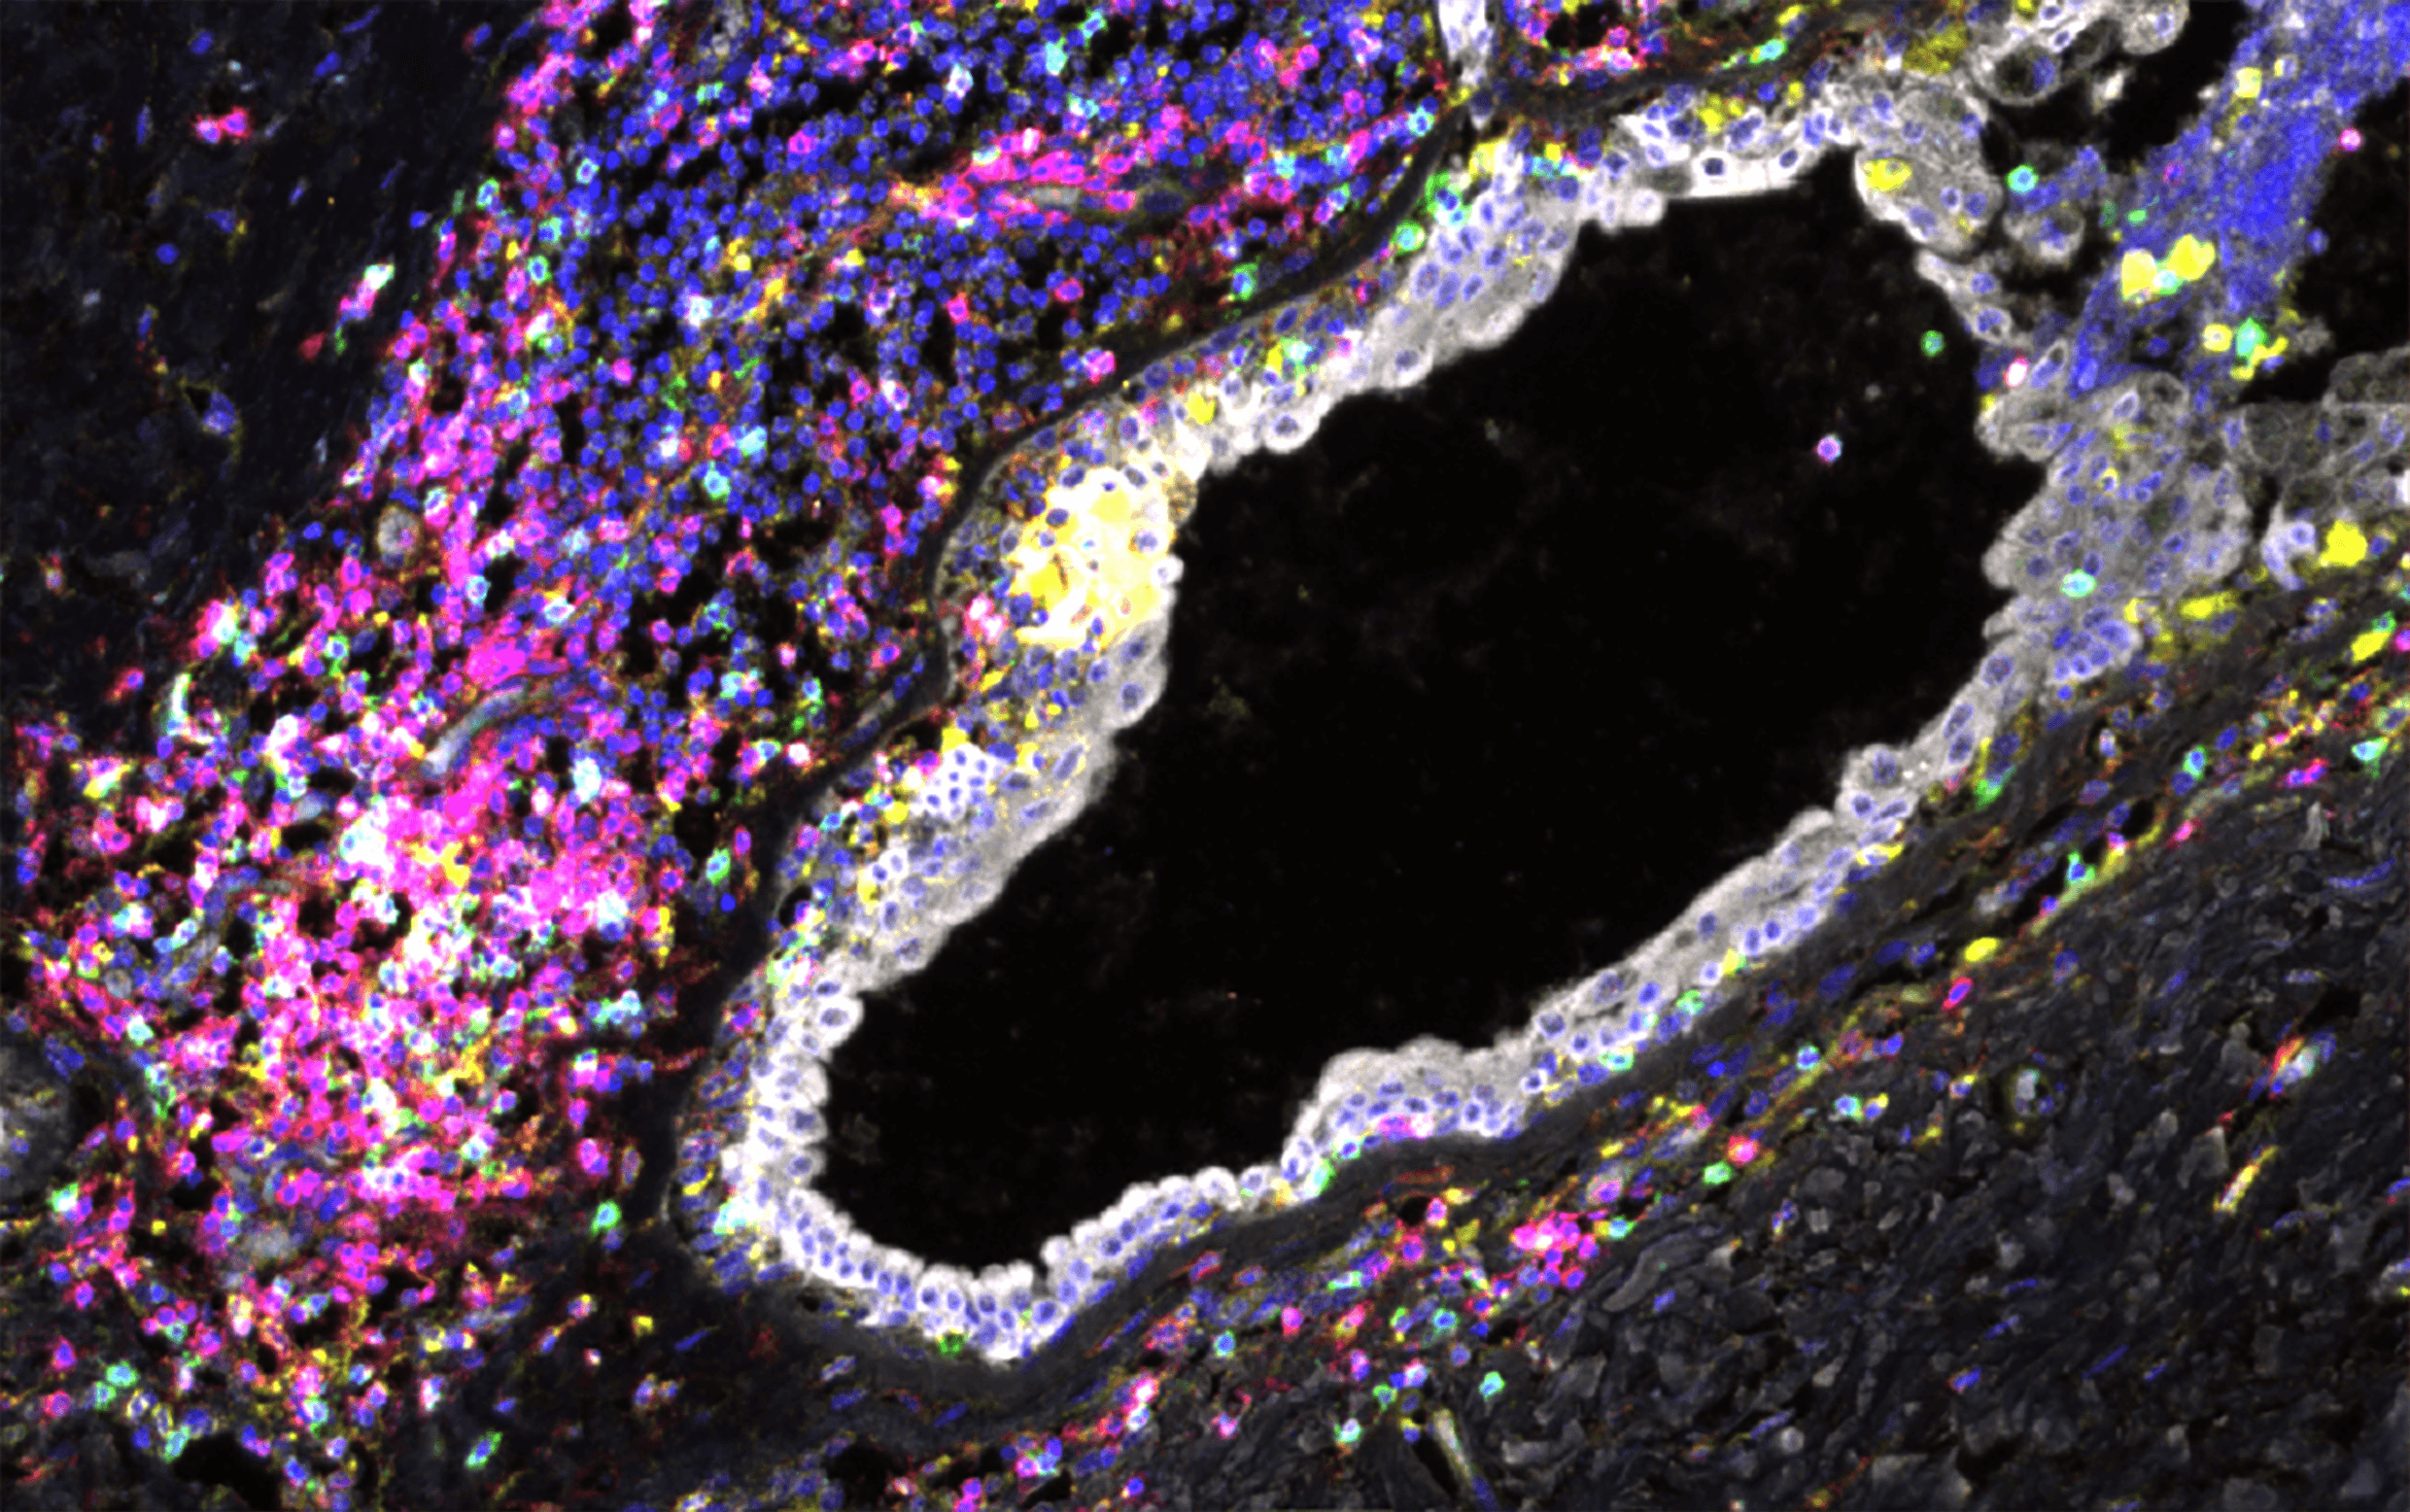

Aims to study which immune cells are responsible for cancer surveillance, the markers of whether they have seen early (or pre-) cancer and if they could have been detected years before clinical diagnosis. It includes an ambitious array of analytic modalities brought together by cutting edge machine learning.

Project leads: Jamie Blundell, Robert Bristow, Evan Lind, Parag Mallick, Benny Chain

Collaborating institutions: University of Cambridge, University of Manchester, OHSU, Stanford University (prior partner), UCL

Exploiting the immune system for cancer early detection

This theme investigates using the adaptive immune system as a means for early cancer detection by characterising immune signatures that associate with early cancer development.

Theme leads: Jamie Blundell (University of Cambridge), Robert Bristow (University of Manchester)